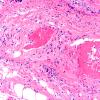

PERIPHERAL NEUROPATHY

11 VASCULITIS - VASCULOPATHY

3 Vasculitis - NOS (10)